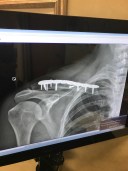

With 9 screws and a metal plate in my right shoulder, it’s a wonder I can even function.